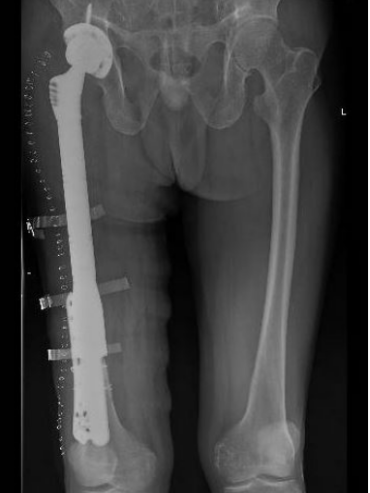

[ 老陶的术前影像(左)与术后影像(右) ]

一味地止痛也不是长久之计,于是老陶又换了一家医院,这次复查髋关节X光片发现右侧股骨颈已断裂。这家医院立即给老陶做右侧髋关节置换手术。手术中发现股骨颈肿瘤,做了肿瘤刮除,但手术中股骨大段劈裂,随即行钢板螺钉固定+钢丝辅助固定。

许宋锋主任初步分析:目前肿瘤仍有残余,右侧股骨劈裂,右腿比左腿长了2公分。唯一值得庆幸的是,癌细胞还没有大范围扩大。经过充分评估后,许宋锋主任建议老陶进行二次手术,扩大肿瘤切除范围,置换新的量身定制的假体。